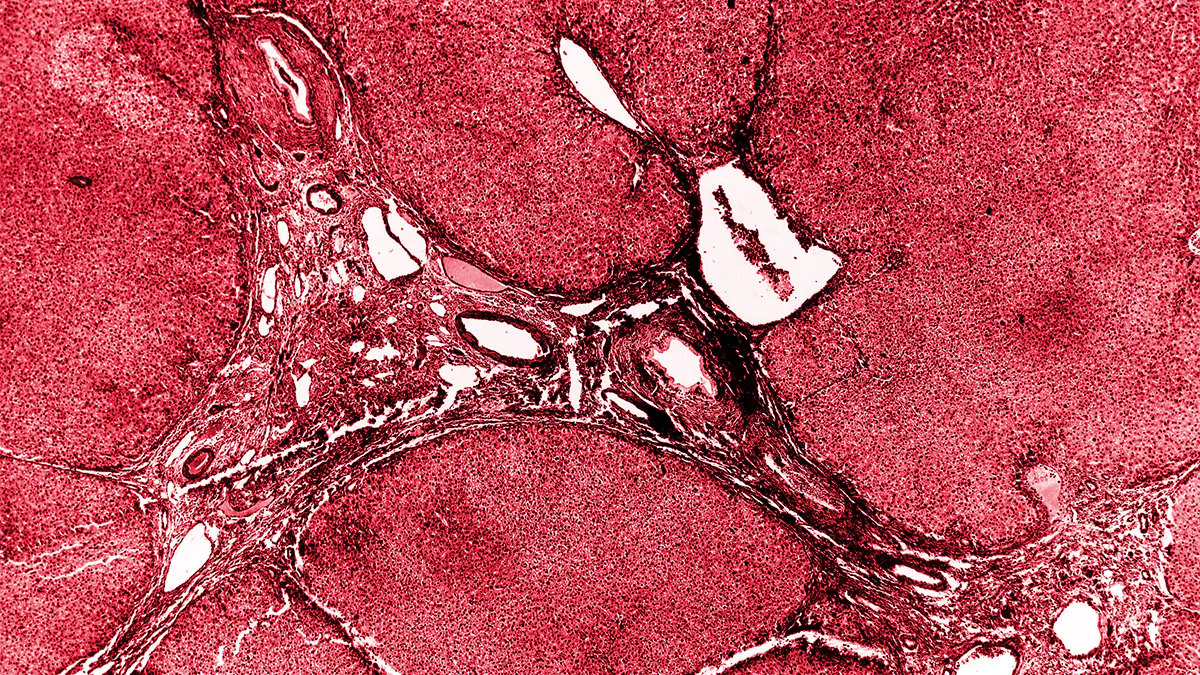

Schistosomiasis is a disease caused by parasitic worms and spread through contact with unsafe water.

Clinical Overview of Schistosomiasis

There are acute and chronic phases of schistosomiasis, along with tests and treatment available.